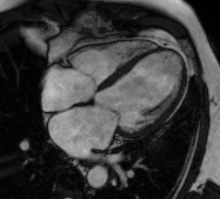

Heart function using cine imaging

Functional and structural information is acquired using bSSFP cine sequences. These are usually retrospectively-gated and have intrinsically high contrast in cardiac imaging due to the relatively high T2:T1 ratio of blood compared to myocardium. Images are typically planned sequentially to achieve the standard cardiac planes used for assessment. Turbulent flow causes dephasing and signal loss allowing valvular disease to be qualitatively appreciated. The left ventricular short axis cines are acquired from base to apex and are used for quantifying end-diastolic and end-systolic volumes, as well as myocardial mass. Tagging sequences excite a grid pattern that deforms with cardiac contraction allowing strain to be assessed.